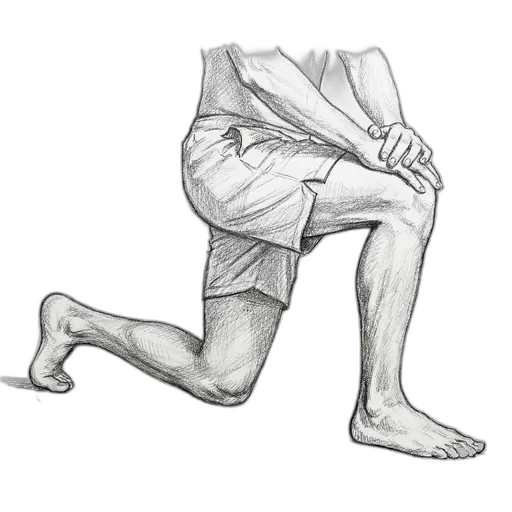

Half-Kneeling Dorsiflexion Mobilization

This mobilization targets the ankle joint itself — specifically the talocrural joint, where your shin bone meets your foot. Sometimes ankle stiffness isn't just tight muscles; the joint capsule itself gets stiff, especially after injury or immobilization. This exercise gently pushes the talus bone (your ankle bone) backward in its socket while improving dorsiflexion (the ability to bend your ankle upward). Think of it as "oiling" the hinge of a stiff door.

What to expect: You should notice improved ankle "bend" within 1–2 weeks. A simple home test: kneel in front of a wall, put your toes 4 inches from the wall, and try to touch your knee to the wall without lifting your heel. Track your progress by increasing the distance — 5 inches is good, 6+ inches is great.

How to do it: Kneel on one knee (a folded towel under the knee helps). Place the other foot flat on the floor in front of you. Keep that front heel firmly on the ground and gently drive the front knee forward over your toes — your knee should track over your 2nd or 3rd toe. You'll feel a deep stretch in the front of the ankle.

| Level | Hold | Reps | Sets | How Often | Tips |

|---|---|---|---|---|---|

| Mild | 5-sec oscillations or 30 sec sustained | 15 | 3 | 1×/day | Oscillate: gentle rhythmic push-and-release at end range. Like rocking a stiff door open a little further each time |

| Moderate | 5-sec oscillations | 10 | 2 | 1×/day | Smaller range of motion — don't force it to end range. Stop immediately if you feel pinching in the front of the ankle |

| Severe | gentle oscillations only | 8 | 1 | every other day | Try the seated version: sit with your foot flat on the floor and gently lean your knee forward over your toes. Skip this if the ankle is still swollen |

How to progress: Increase the depth of the lunge. Add a resistance band looped around the ankle (pulling backward) for a posterior glide mobilization — this gives the joint a mechanical advantage. Measure progress with the knee-to-wall test.

⚠ When to skip this: Skip with an acute ankle fracture. If you have a bone spur at the front of the ankle (anterior impingement), this may cause pinching — stop if you feel a sharp catch in the front of the joint. Wait for post-surgical clearance.